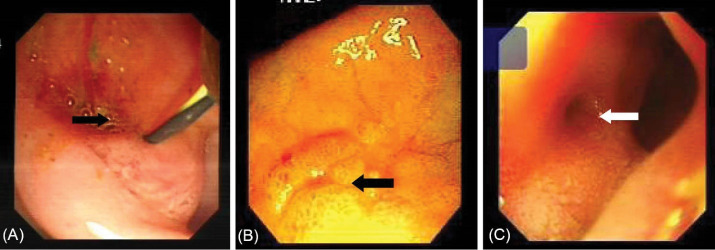

Table 2 shows detailed information about the endoscopic and cholangiographic findings and therapeutic procedure in all patients. Peptic ulcer in different stages, ranging from a scar mark alone to a crater with varying size, was found in the duodenum in 11 (37%) patients. In two patients (6.8%), we observed gastric peptic ulcer (3×2 cm and 2×1 cm in diameter, respectively) located to the incisura angularis and its benign nature was confirmed by biopsy. Ectopic opening opened into the antrum in 2 (6.8%) patients and into the first part of the duodenum in 27 (93%) patients. Both patients with ectopic opening into the first part of the duodenum and into the antrum did not have the classic appearance of the ampulla of Vater and there was a slit-like appearance (Figure 1A), ill-defined mucosal edematous area (Figure 1B) or a circular hole (Figure 1C). In patients with ectopic opening located in the first part of the duodenum, the orifice was located in the posterior wall of the first part of the duodenum. In two patients with ectopic opening located in the antrum, the orifice was located between the incisura angularis and pyloric canal. In 5 out of 29 (17%) patients, the bile duct and pancreatic duct opened to the duodenal bulb separately (Figure 2). All patients had abnormal appearance of the duodenal bulb. Although there was no duodenal ulcer in those patients with ectopic opening to the antrum, both patients had duodenal deformity and apical stenosis. Duodenal deformity associated with apical stenosis was found in 21 out of 29 (72%) patients (Figure 3). None of patients with apical stenosis required balloon dilation. Eight out of 21 (38%) patients with apical stenosis had active duodenal ulcer. Thirteen out of 21 (62%) patients with duodenal deformity and apical stenosis had no visible active ulcer or scar in their duodenum and antrum. Copious amount of bile and/or bile sediment in the stomach was seen in all patients.

This opening anomaly is diagnosed by visualization of the opening site of CBD by endoscopy and cholangiography. The typical appearance of the ampulla of Vater is absent and a slit-like orifice is seen during endoscopic examination. This slit-like opening configuration may reflect a poorly developed or absence of the sphincter of Oddi. In a majority of patients with ectopic opening of CBD into the first part of the duodenum, there is apical stenosis associated with duodenal ulcer.1,11,14–17 There are a few case reports showing that an opening of the CBD into the antrum might cause gastric ulcer.5,10 Excessive bile, bile precipitates1,3 and small gallstones4,5 in the stomach were detected in patients with ectopic opening of the CBD into the first part of the duodenum and into the antrum. The cause of apical stenosis and increased incidence of peptic ulcer in patients with this abnormality is unknown. It has been speculated that bile acids usually precipitate at acidic pH and becomes harmless. However, under alkaline condition where the pH is higher, constant exposure of the duodenal bulb and gastric mucosa to bile acids can induce mucosal inflammation, ulcer and stenosis.3 In our case series, there were copious amounts of bile and/or bile sediment in the stomach and slit-like orifice in all patients. The presence of duodenal deformity together with apical stenosis in 21 out of 29 (72%) patients and active duodenal ulcer in 8 out of 21 (38%) patients with apical stenosis was compatible with previously reported findings in patients with this anomaly. Thirteen out of 21 (62%) patients with duodenal deformity and apical stenosis had no visible active ulcer or scar in their duodenum and antrum. These findings may support the possibility that the presence of apical stenosis in these patients may be related to a congenital abnormality or may be related to fibrosis caused by a completely healed duodenal ulcer.